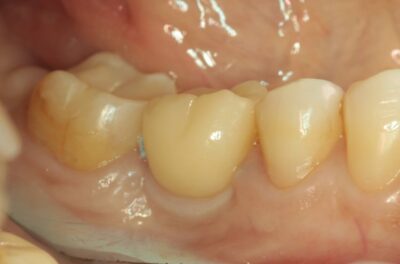

Протезирование коронками из диоксида циркония, после эндодонтического лечения — Исламов Л.А.(01.04.2026)